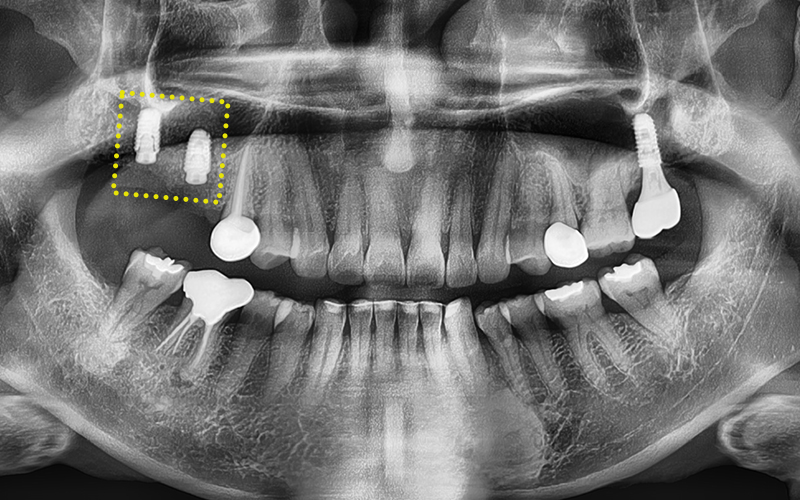

✅ 치료 완료 후 보철물까지 완성!

교합을 섬세하게 고려하여

정밀하게 보철작업까지

완료된 모습입니다!

✅ 전 > 후

2024.11.22

▼ ▼ ▼

2025.04.15